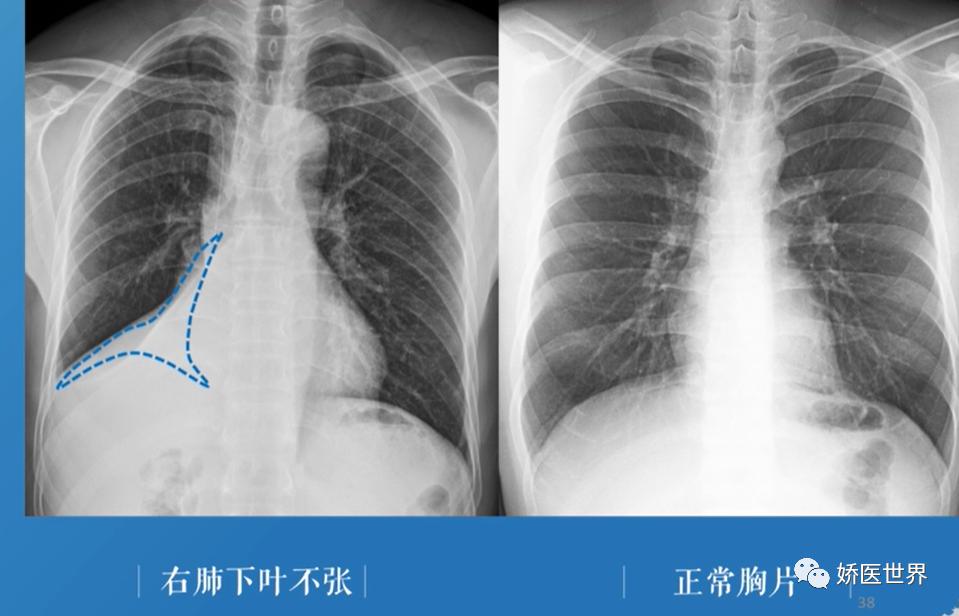

③右肺下叶不张